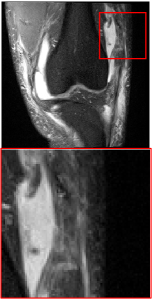

Figure 5 provides the qualitative comparison of the various methods on the four datasets at a scale of 4. The top, second, third, and bottom rows are the SR results under the FastMRI, clinical brain, clinical tumor and clinical pelvic datasets, respectively. The red boxes indicate the zoom-in region of complicated anatomical structures along with their corresponding error maps. Note that the brighter textures in the error maps, the lower the quality of the reconstructed images. As can be seen, compared to methods based on Transformers and CNNs, diffusion-based methods like DisC-Diff and DiffMSR (Ours) are capable of reconstructing high-realistic images with promising reconstruction metric scores (PSNR and SSIM). Nevertheless, while DisC-Diff can reconstruct high-precision MR images, it does not preserve the structure present in the original HR images, introducing some additional information that can affect medical diagnosis. In contrast, our method combines DM and PLWformer, which can preserve the original image’s structure while restoring high-frequency information.

In this section, we present more visual qualitative comparisons. Figures 8, 9, 10, and 11 show the reconstruction results of each method in FastMRI, clinical brain, clinical tumor, and clinical pelvic, respectively. As can be seen, although DisC-Diff can reconstruct MR images with high-frequency information, it fails to preserve the structure and content of the original Target HR image effectively, resulting in image distortion. In contrast, our proposed DiffMSR can restore high-frequency information while preserving the structure of the original HR image, indicating the effectiveness of the joint use of DM and PLWformer.